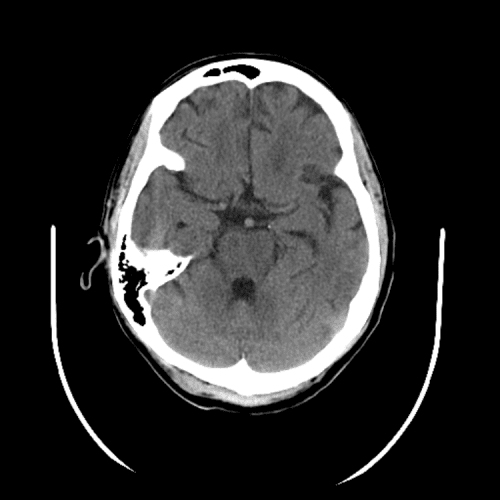

PCA infarct

Case #2